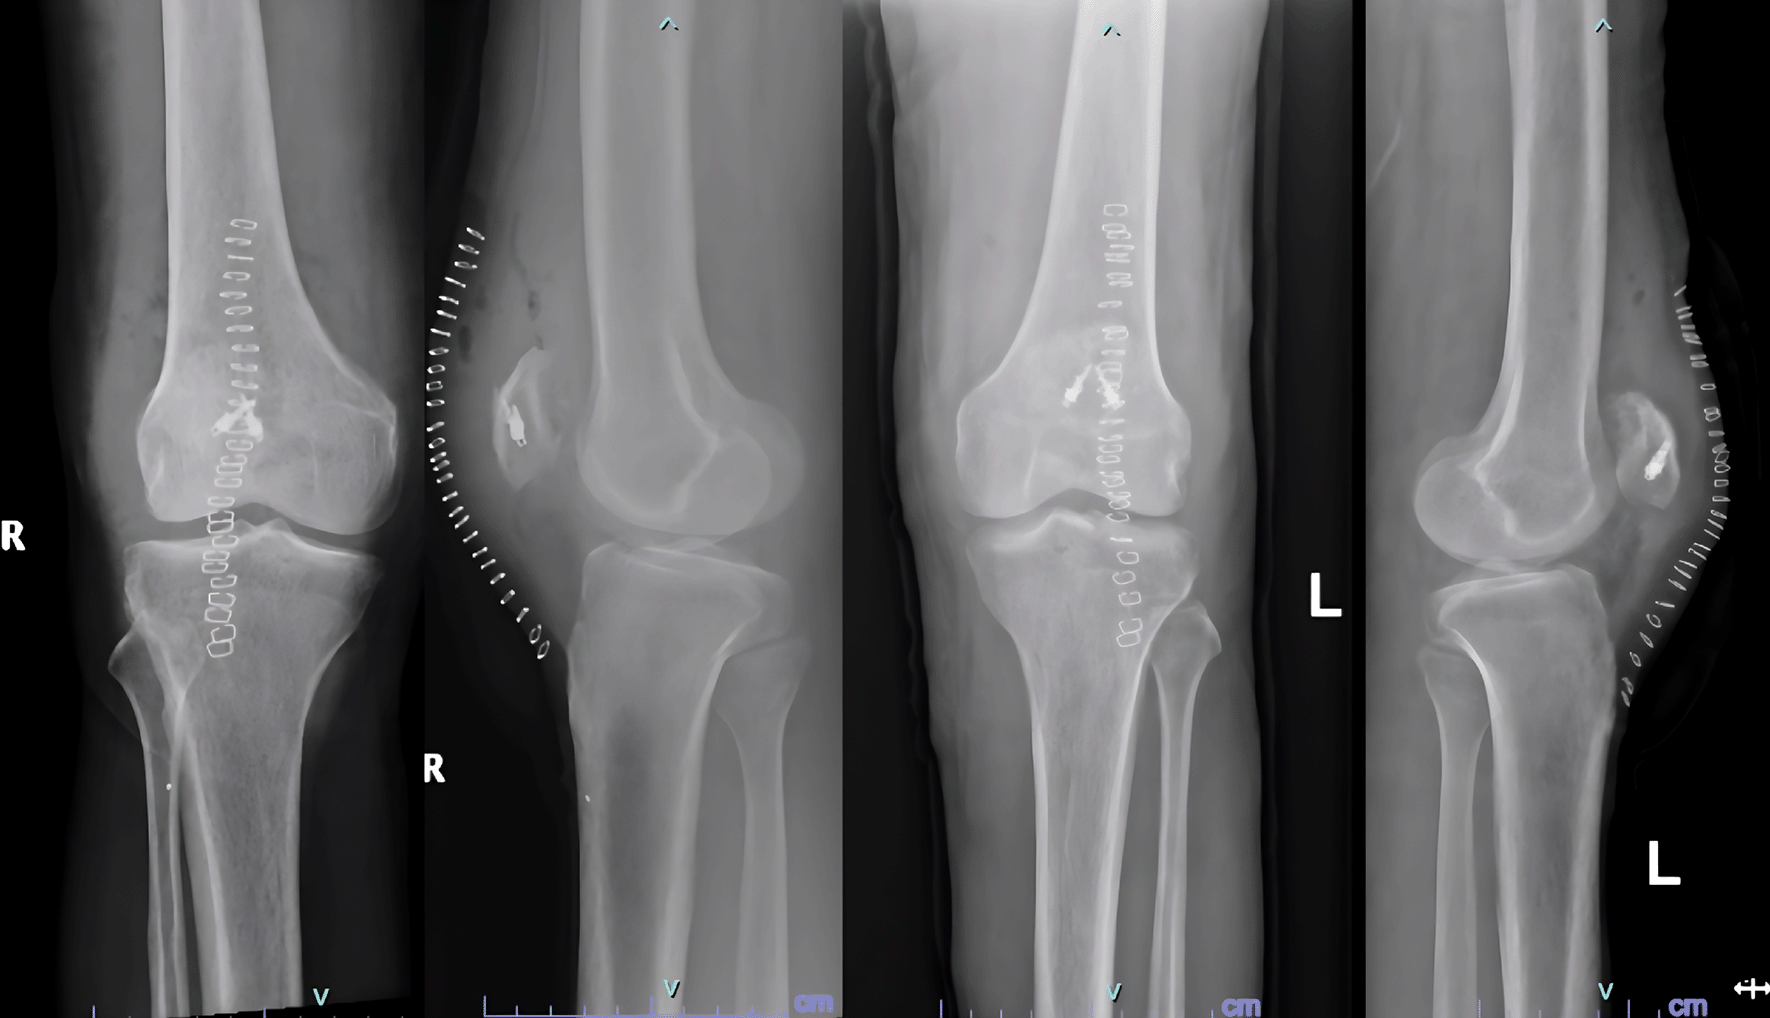

Examination revealed bilateral patella alta and boggy swelling in both knees with grade 0 power in bilateral knee extension. Imaging revealed isolated patella alta without any avulsed bony edges (Figure 5).

Figure 5. Patella Alta noted in case 3 due to quadriceps rupture.

He was diagnosed with bilateral patellar tendon rupture and underwent open repair during which severe fraying of the tendons was noted (Figure 6). Robust repair was performed using non-absorbable sutures in a mattress pattern (Figure 7). He was given bilateral long knee immobilizers for 6 weeks to protect the repair, following which he was started on assisted ambulation with walker support over the next 4 weeks. At the final review at 6 months, he had grade 5/5 power in both his knee extensors with no appreciable lag on either side.

Figure 7. Post operative radiographs of 3 after patellar tendon repair.